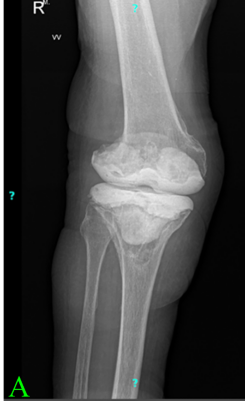

A Rare and Interesting Case of Sciatic Nerve Compression Due to Proximal Femoral Osteochondroma in a Young Adult – A Case Report

Ninad Kishor Honwadkar , Eknath Deosing Pawar , Abhiram T V , Aravind Chanal , Atharva Alaspure